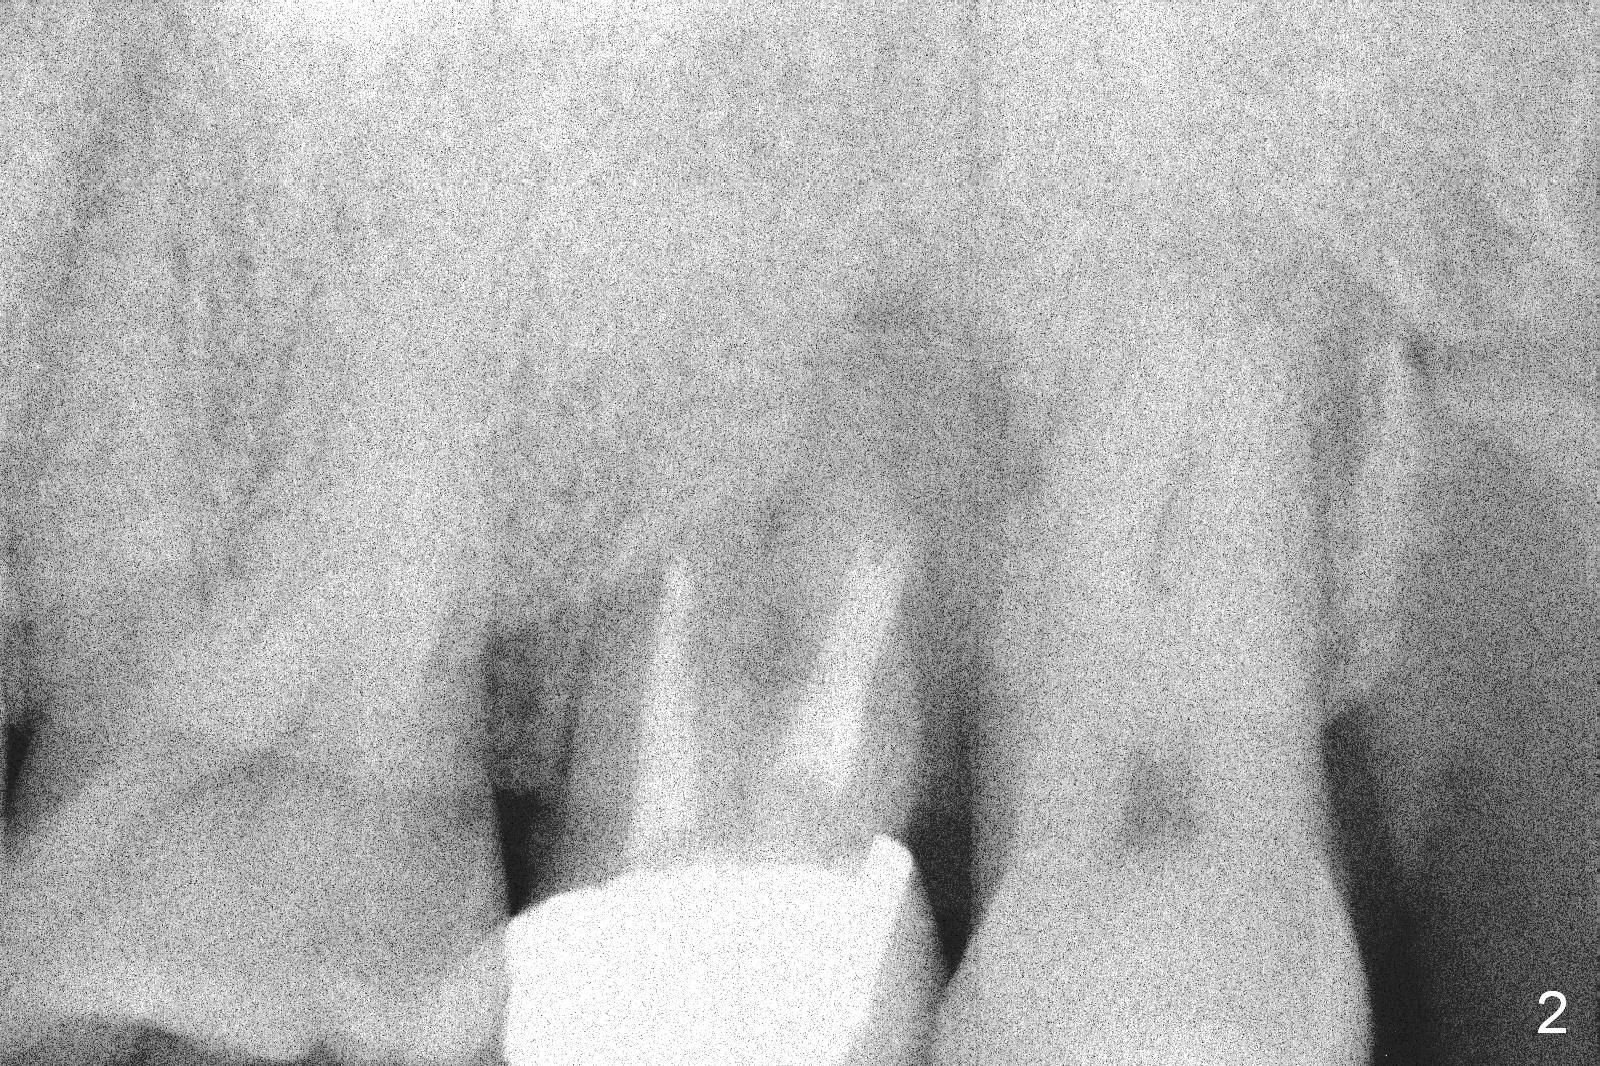

A 47-year-old man (LW) agrees to have the tooth #15 (Fig.1) extracted for implant after 4-year delay (Fig.2). A 20 mm long implant will have at least 6 mm native bone for stabilization (Fig.3). Bone density seems to be high. Use Bicon drill and reamers until 3.5 mm, followed by 5x20 mm Tatum tapered tap and PA.